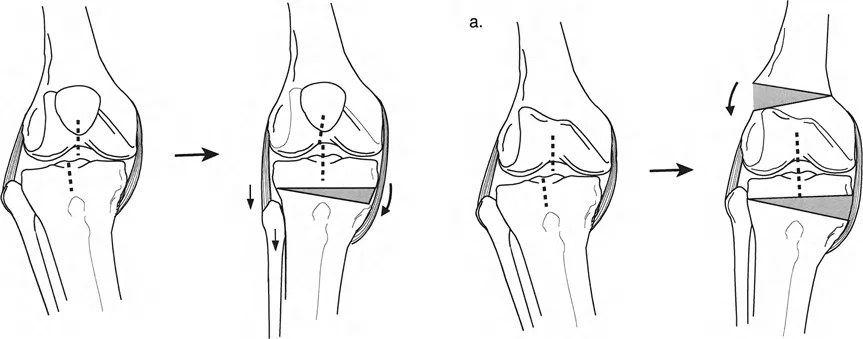

تتضمن جراحة قطع العظم قطع العظم (عادة عظم الفخذ أو الساق) وإعادة تشكيله لتغيير محاذاة المفصل. يمكن أن يكون القطع:

- قطع العظم بالوتد المفتوح (Opening Wedge Osteotomy): يتم عمل قطع في العظم ثم فتح فجوة صغيرة تُملأ غالبًا بطعم عظمي، مما يطيل الجزء المعني من العظم ويصحح المحاذاة.

- قطع العظم بالوتد المغلق (Closing Wedge Osteotomy): يتم إزالة جزء صغير من العظم على شكل وتد، ثم تُغلق الفجوة وتُثبت العظام، مما يقصر الجزء المعني ويصحح المحاذاة.

علاج خشونة المفصل أحادي الحجرة الإنسية (MCOA)

غالبًا ما ترتبط خشونة الركبة الإنسية بالانحراف الأفحج (Genu Varum). يهدف العلاج إلى تحويل الحمل من الحجرة الإنسية المتضررة إلى الحجرة الوحشية السليمة.

- قطع العظم الظنبوبي العلوي (High Tibial Osteotomy - HTO):

- يُعد هذا الإجراء الأكثر شيوعًا لعلاج خشونة الركبة الإنسية مع الانحراف الأفحج.

- يتم عمل قطع في الجزء العلوي من عظم الساق (الظنبوب)، ثم يتم تصحيح الانحراف الأفحج عن طريق فتح وتد (Opening Wedge) على الجانب الإنسي أو إزالة وتد (Closing Wedge) على الجانب الوحشي.

علاج خشونة المفصل أحادي الحجرة الوحشية (LCOA)

ترتبط خشونة الركبة الوحشية غالبًا بالانحراف الأروح (Genu Valgum). يهدف العلاج إلى تحويل الحمل من الحجرة الوحشية المتضررة إلى الحجرة الإنسية السليمة.

- قطع العظم الفخذي البعيد (Distal Femoral Osteotomy - DFO):

- يُعد الخيار الأكثر شيوعًا، حيث يتم عمل قطع في الجزء السفلي من عظم الفخذ لتصحيح الانحراف الأروح.